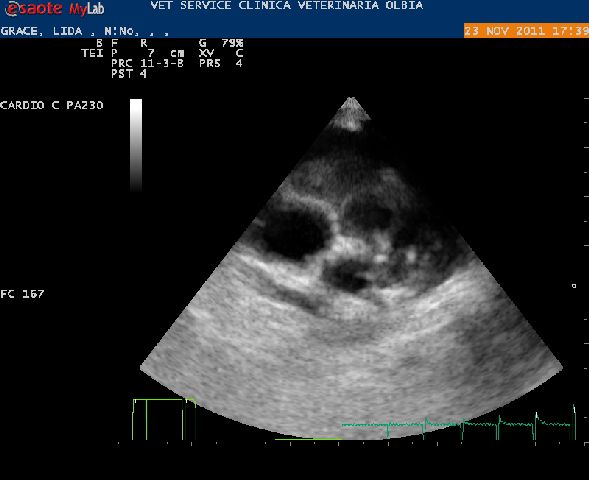

30-11-2011 - E cosi' come vi avevamo anticipato eccoci di ritorno dalla Clinica Malpensa a Samarate. La sua diagnosi confermata dal Dott. Santilli:

Grave stenosi polmonare a tipo misto con piccolo difetto setto interventricolare perimembranoso.

Ispessimento cuspidi polmonari con fusione dei lembi e doming. Marcata dilatazione arteria polmonare principale con annulus normale (12 mm). Marcata ipertrofia concentrica settoparietale destra con iperecogenicità subendocardica e grave sovraccarico pressorio ventricolare destro. Evidente lieve destro-posizione aortica con piccolo difetto setto interventricolare perimembranoso.

Stenosi polmonare grave e dinamica moderata (3,93 m/sec). Modesto flusso transettale.Intervento tra 15 gg.

Per il momento la piccola dovrà prendere un farmaco, Atenololo.

Il dott. Santilli è sato chiarissimo, la patologia di Greta è una di quelle che porta inesorabilmente alla morte in brevissimo tempo ma ha ribadito nello stesso tempo che l' intervento è molto rischioso ma è l' unica possibilità per vivere.